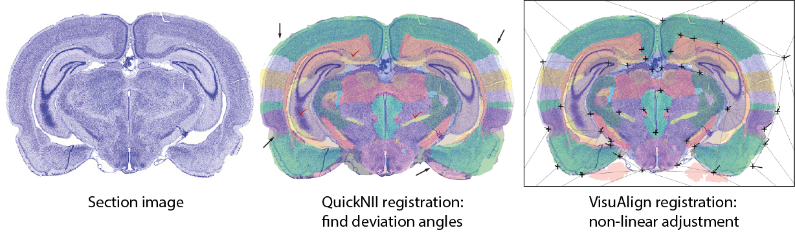

QuickNII and VisuAlign

Tools for anatomical landmark based registration of mouse and rat 2D brain images to 3D reference atlases.